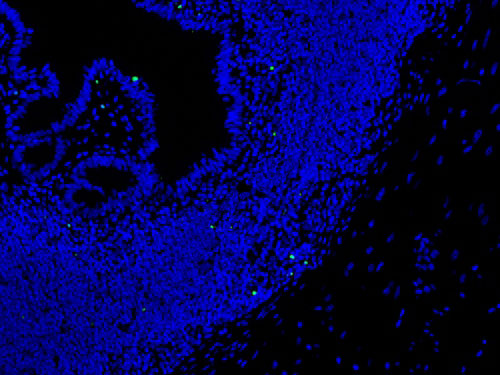

實驗結果展示:

TUNEL(熒光)檢測-小鼠卵巢

TUNEL(熒光)檢測-小鼠腸